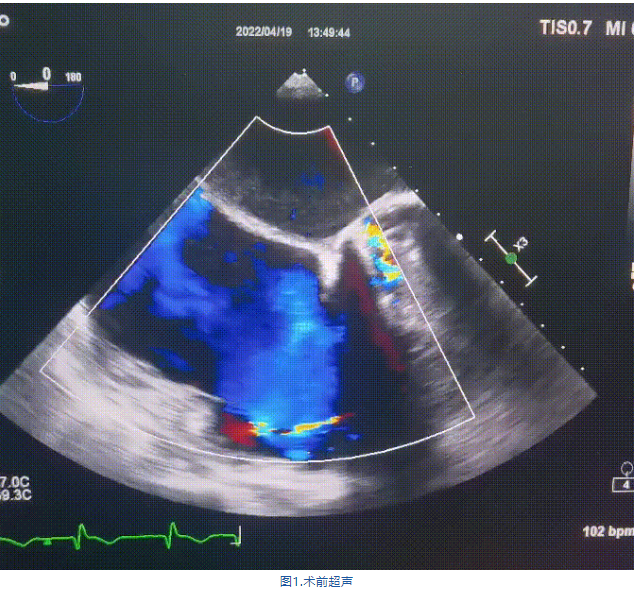

術前超聲提示:

1.右心、左房明顯增大;

2.二尖瓣人工機械瓣功能正常,無瓣周漏;

3.三尖瓣環巨大擴張,收縮期瓣葉對合不攏,收縮期三尖瓣房側見大量反流信號,反流面積15-20cm²,TRVmax:240cm/s,跨瓣壓差:23 mmHg。